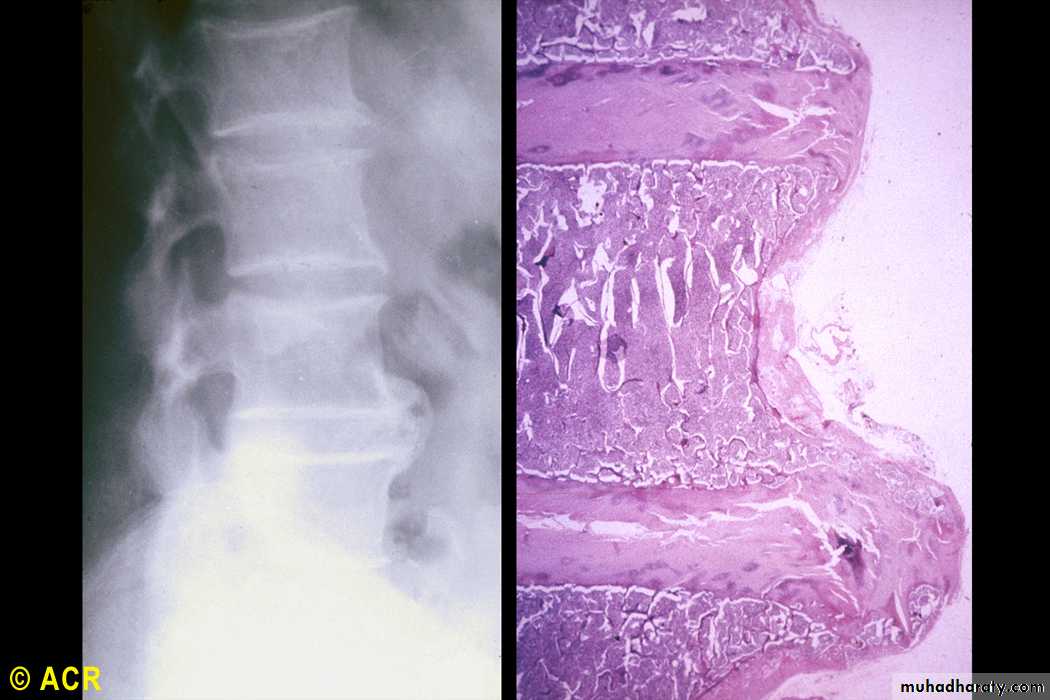

Lumbar vertebrae, osteophytes(radiograph and photomicrograph)